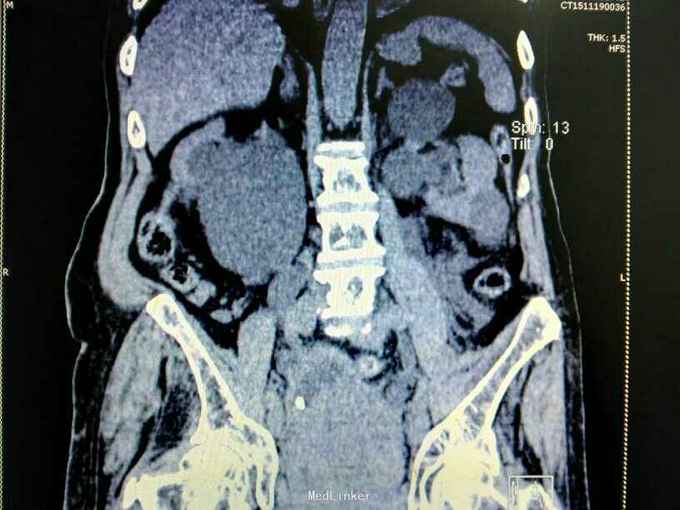

男性,87岁,进行性排尿困难10年,小便不能自解2天入院。无血尿,无发热、腰痛。一直口服藏药治疗前列腺增生症。既往无高血压、糖尿病。

腹部明显膨隆。耻骨上膀胱区扣浊。肾区无扣痛。尿常规少许白细胞。肌酐506,电解质正常。Hb116。

前列腺增生症 尿潴留 双肾积水 肾功能不全,膀胱结石,尿路感染,双肾多发囊肿。给予留置导尿,间断分次放尿后,出现肉眼血尿,持续膀胱冲洗,颜色较红,伴血凝块间断堵管。